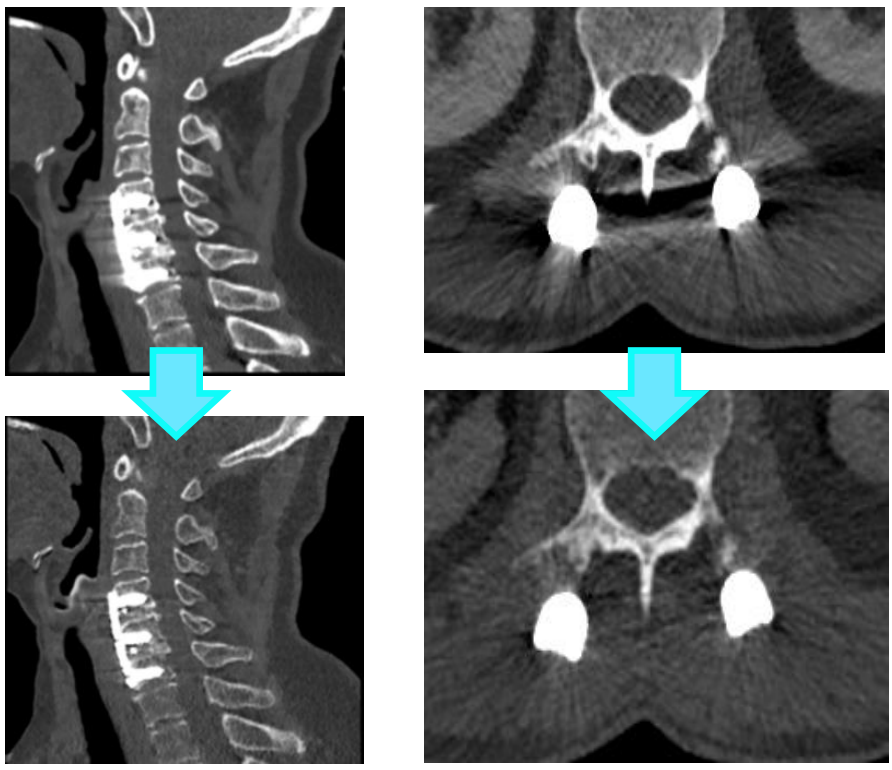

能谱金属伪影去除

支持多部位金属伪影去除,可一键生成去金属伪影效果最佳的图像,校准金属伪影范围能精确到距离金属3cm,减少术后金属伪影影响,有效抑制常见的金属伪影及其他射线硬化伪影,从而提升图像细节。

利用CT能谱单能量图像结合MARS能消除硬化伪影,能够在颅脑成像、颅内脑动脉瘤栓塞术后及骨与关节金属植入物复查中获得良好的成像效果,为临床诊断提供有效信息。